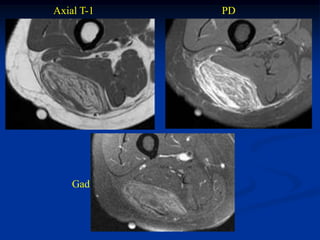

Case #296

24 year female with hemangioma forearm with phleboliths

Case #297

phlebolith

6 year female

hemangioma forearm

Case #297.1                    Hemangioma forearm

Cor T-1                          Gad

18 year old female with forearm mass for years

Axial T-1

Axial Gad

Case #297.2     Hemangioma forearm

46 yr male with

tender soft mass

forearm for years

Cor T-1   T-2   Gad

Sag T-1   T-2   Gad

Axial T-1         T-2

Gad

Case #296 24 yearfemale with hemangioma forearm with phleboliths

• 306.

Case #297 phlebolith 6 year female hemangioma forearm

• 307.

Case #297.1 Hemangioma forearm Cor T-1 Gad 18 year old female with forearm mass for years

• 308.

• 309.

Case #297.2 Hemangioma forearm 46 yr male with tender soft mass forearm for years

• 310.

• 311.

• 312.

Axial T-1 T-2 Gad